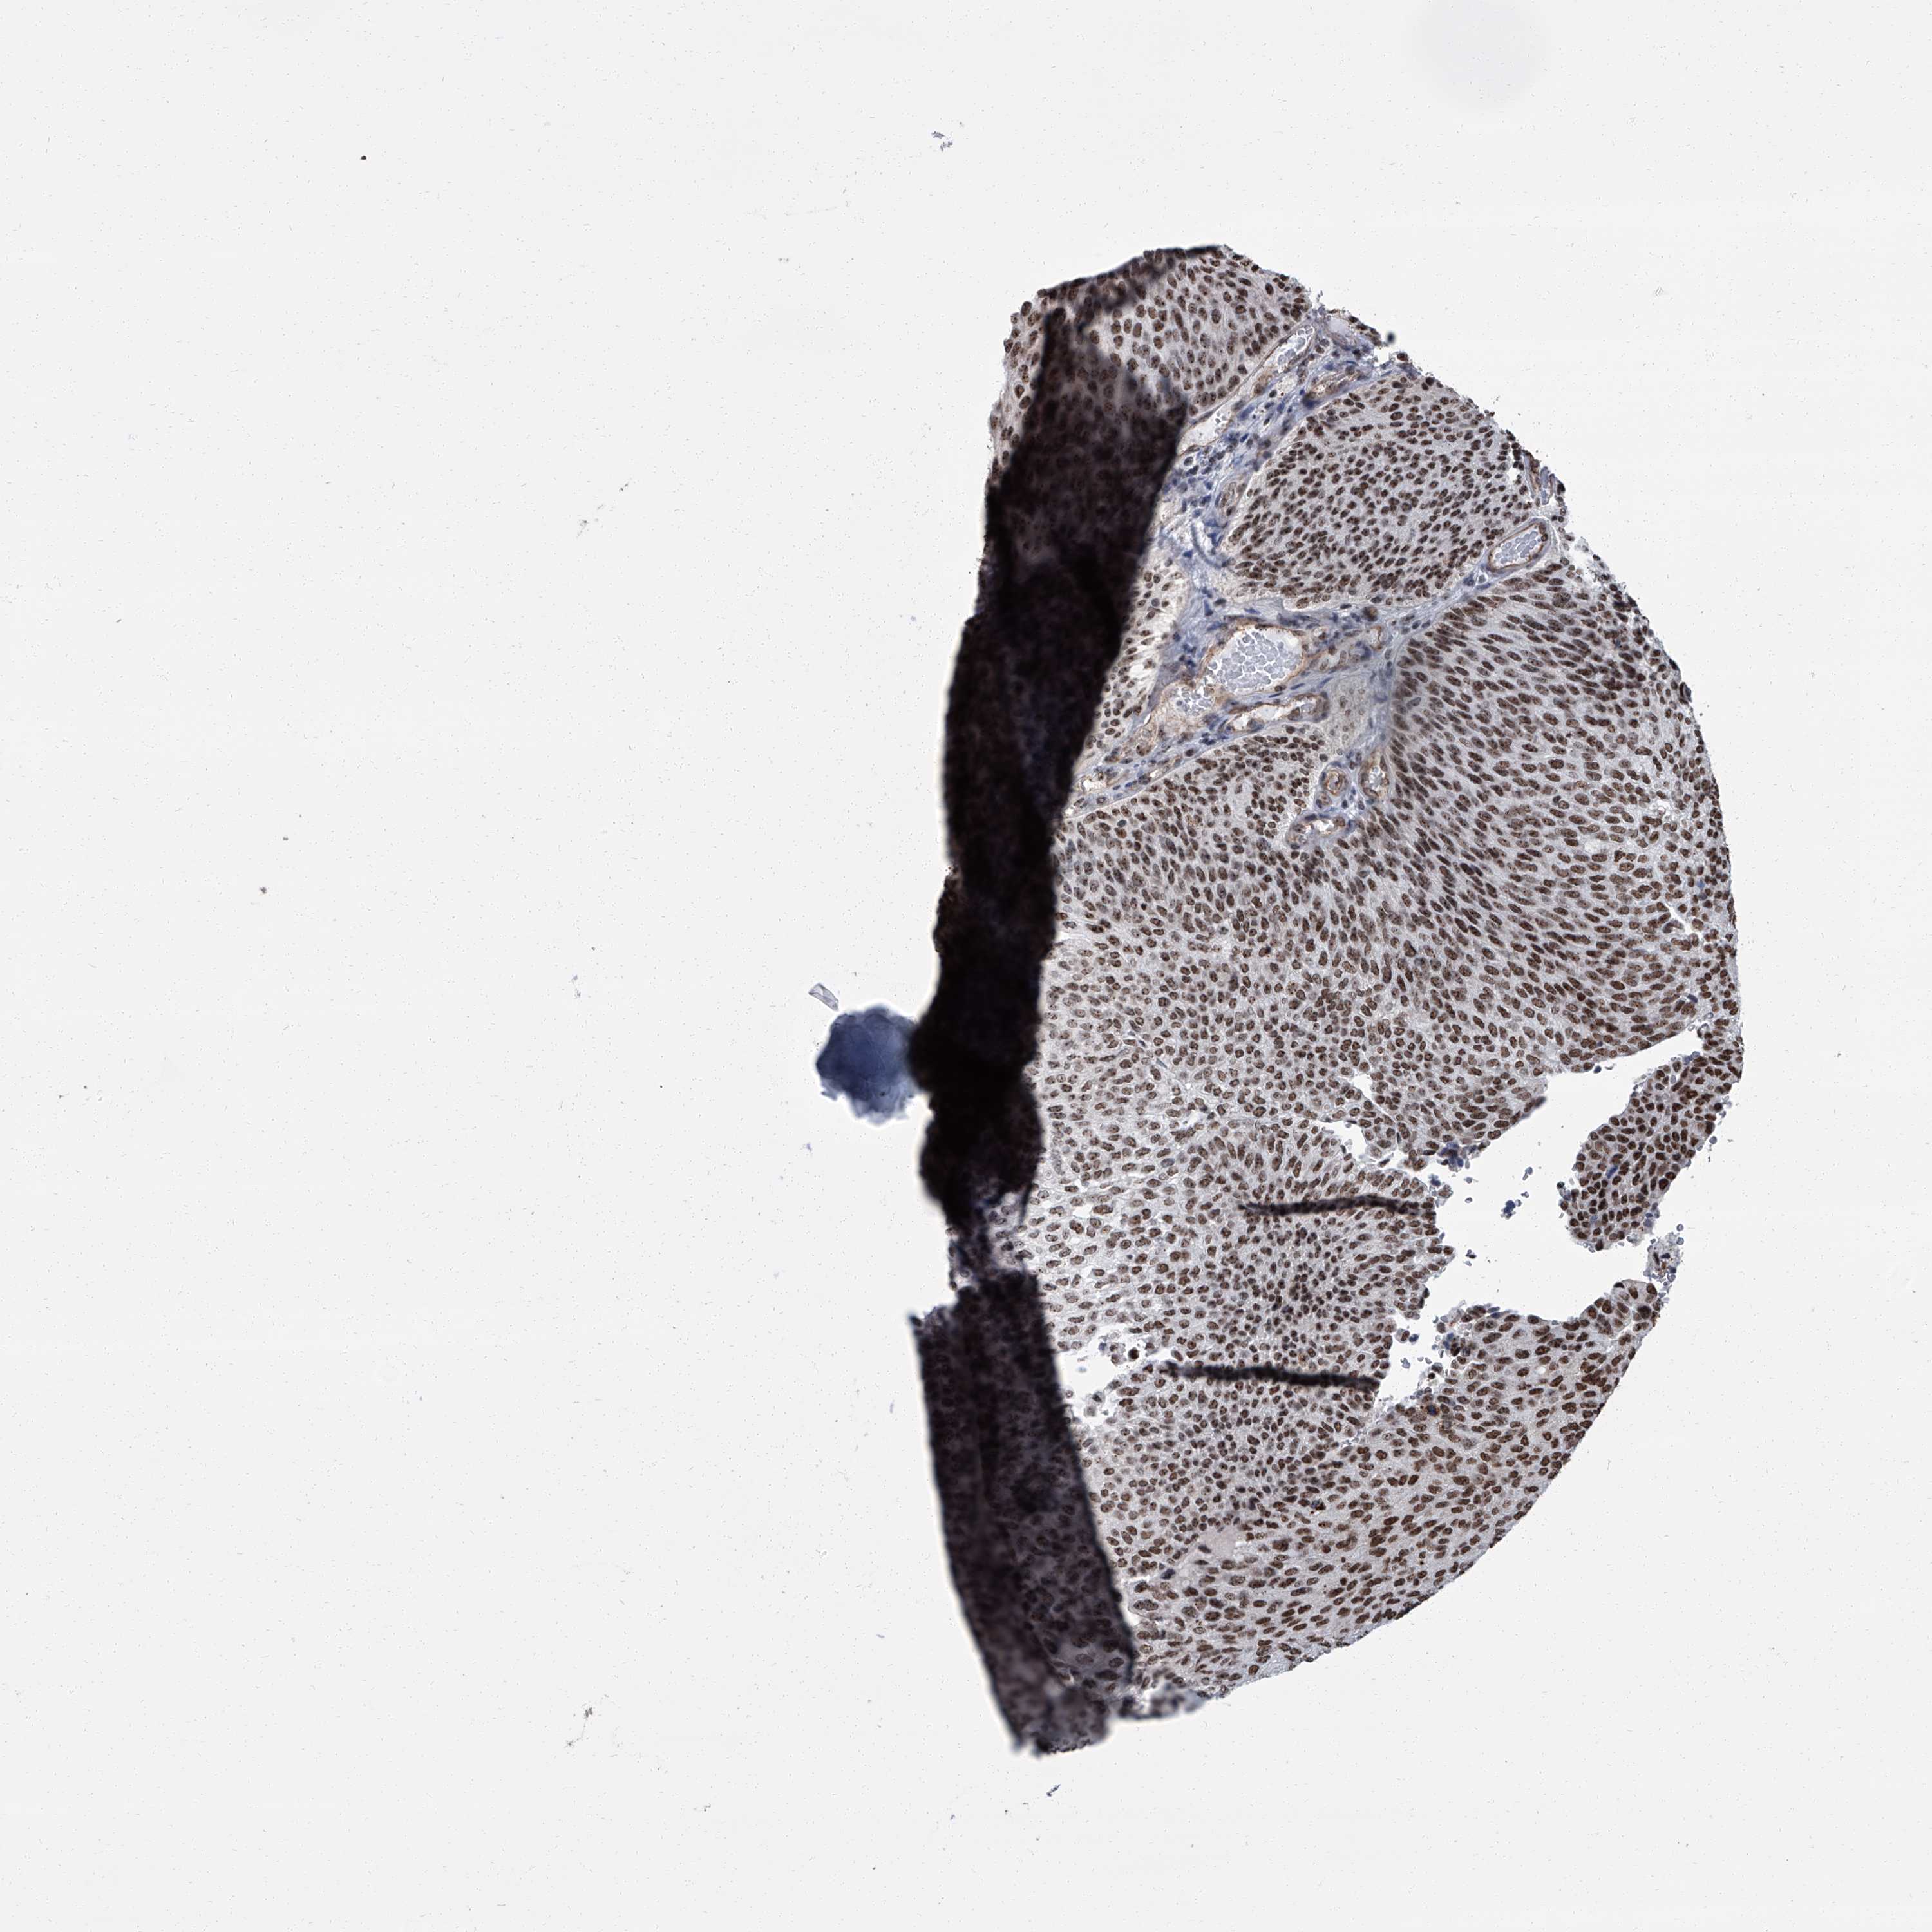

UROTHELIAL CANCER - Protein expressioni

A mouse-over function shows sample information and annotation data. Click on an image to view it in a full screen mode. Samples can be filtered based on level of antibody staining by selecting one or several of the following categories: high, medium, low and not detected. The assay and annotation is described here.

Antibody stainingi

Antibody staining in the annotated cell types in the current human tissue is reported as not detected, low, medium, or high, based on conventional immunohistochemistry profiling in selected tissues. This score is based on the combination of the staining intensity and fraction of stained cells.

Each image is clickable and will lead to virtual microscopy that enables deeper exploration of all samples and also displays staining intensity scores, fraction scores and subcellular localization as well as patient and tissue information for each sample.

Antibody HPA031215

Antibody HPA031216

Urothelial carcinoma, Low grade